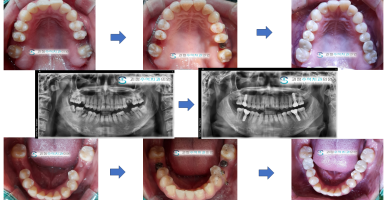

임플란트 식립할 공간이 부족해요

오랜기간 방치되어 임플란트 심을 공간이 부족해서 부분교정으로 임플란트 공간을 확보하여 임플란트를 완성한 사례입니다.